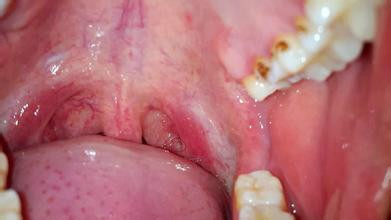

一般来说,卡住鱼刺的位置有三个:左右扁桃体处,喉咙梨状窝处和食道.

可以 先用勺柄压住 舌头 再有 照亮喉咙的 情况下 能看到 鱼刺 就用